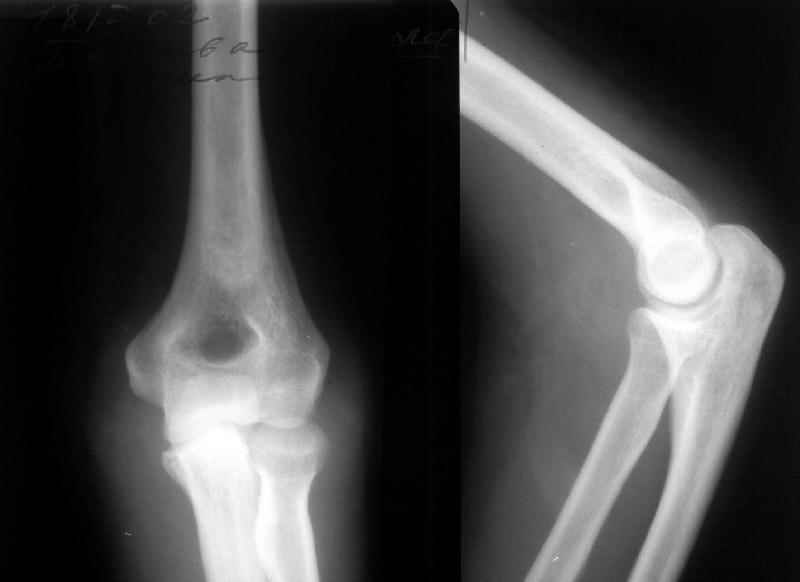

A female 48 years old sustained multiple injuries after fall from 5th floor 28/04/02. Among other injuries there was open posterior elbow dislocation (see attachment). It was reduced and the wound at the medial side of the joint debrided at the initial hospital. May 7 she was transferred to us. The wound healed primarily.

Yesterday (3 weeks post reduction) the plaster was removed to start motions. Gross elbow instability was revealed - the forearm easily can be displaced medially, and reduced back. Recent films with and without subluxation also attached.

What to do? Continue plaster for some more weeks? Revision and repair of medial collateral ligament? XF with hinges? Today the elbow ROM is about 60/150 (with 180 as full extension).